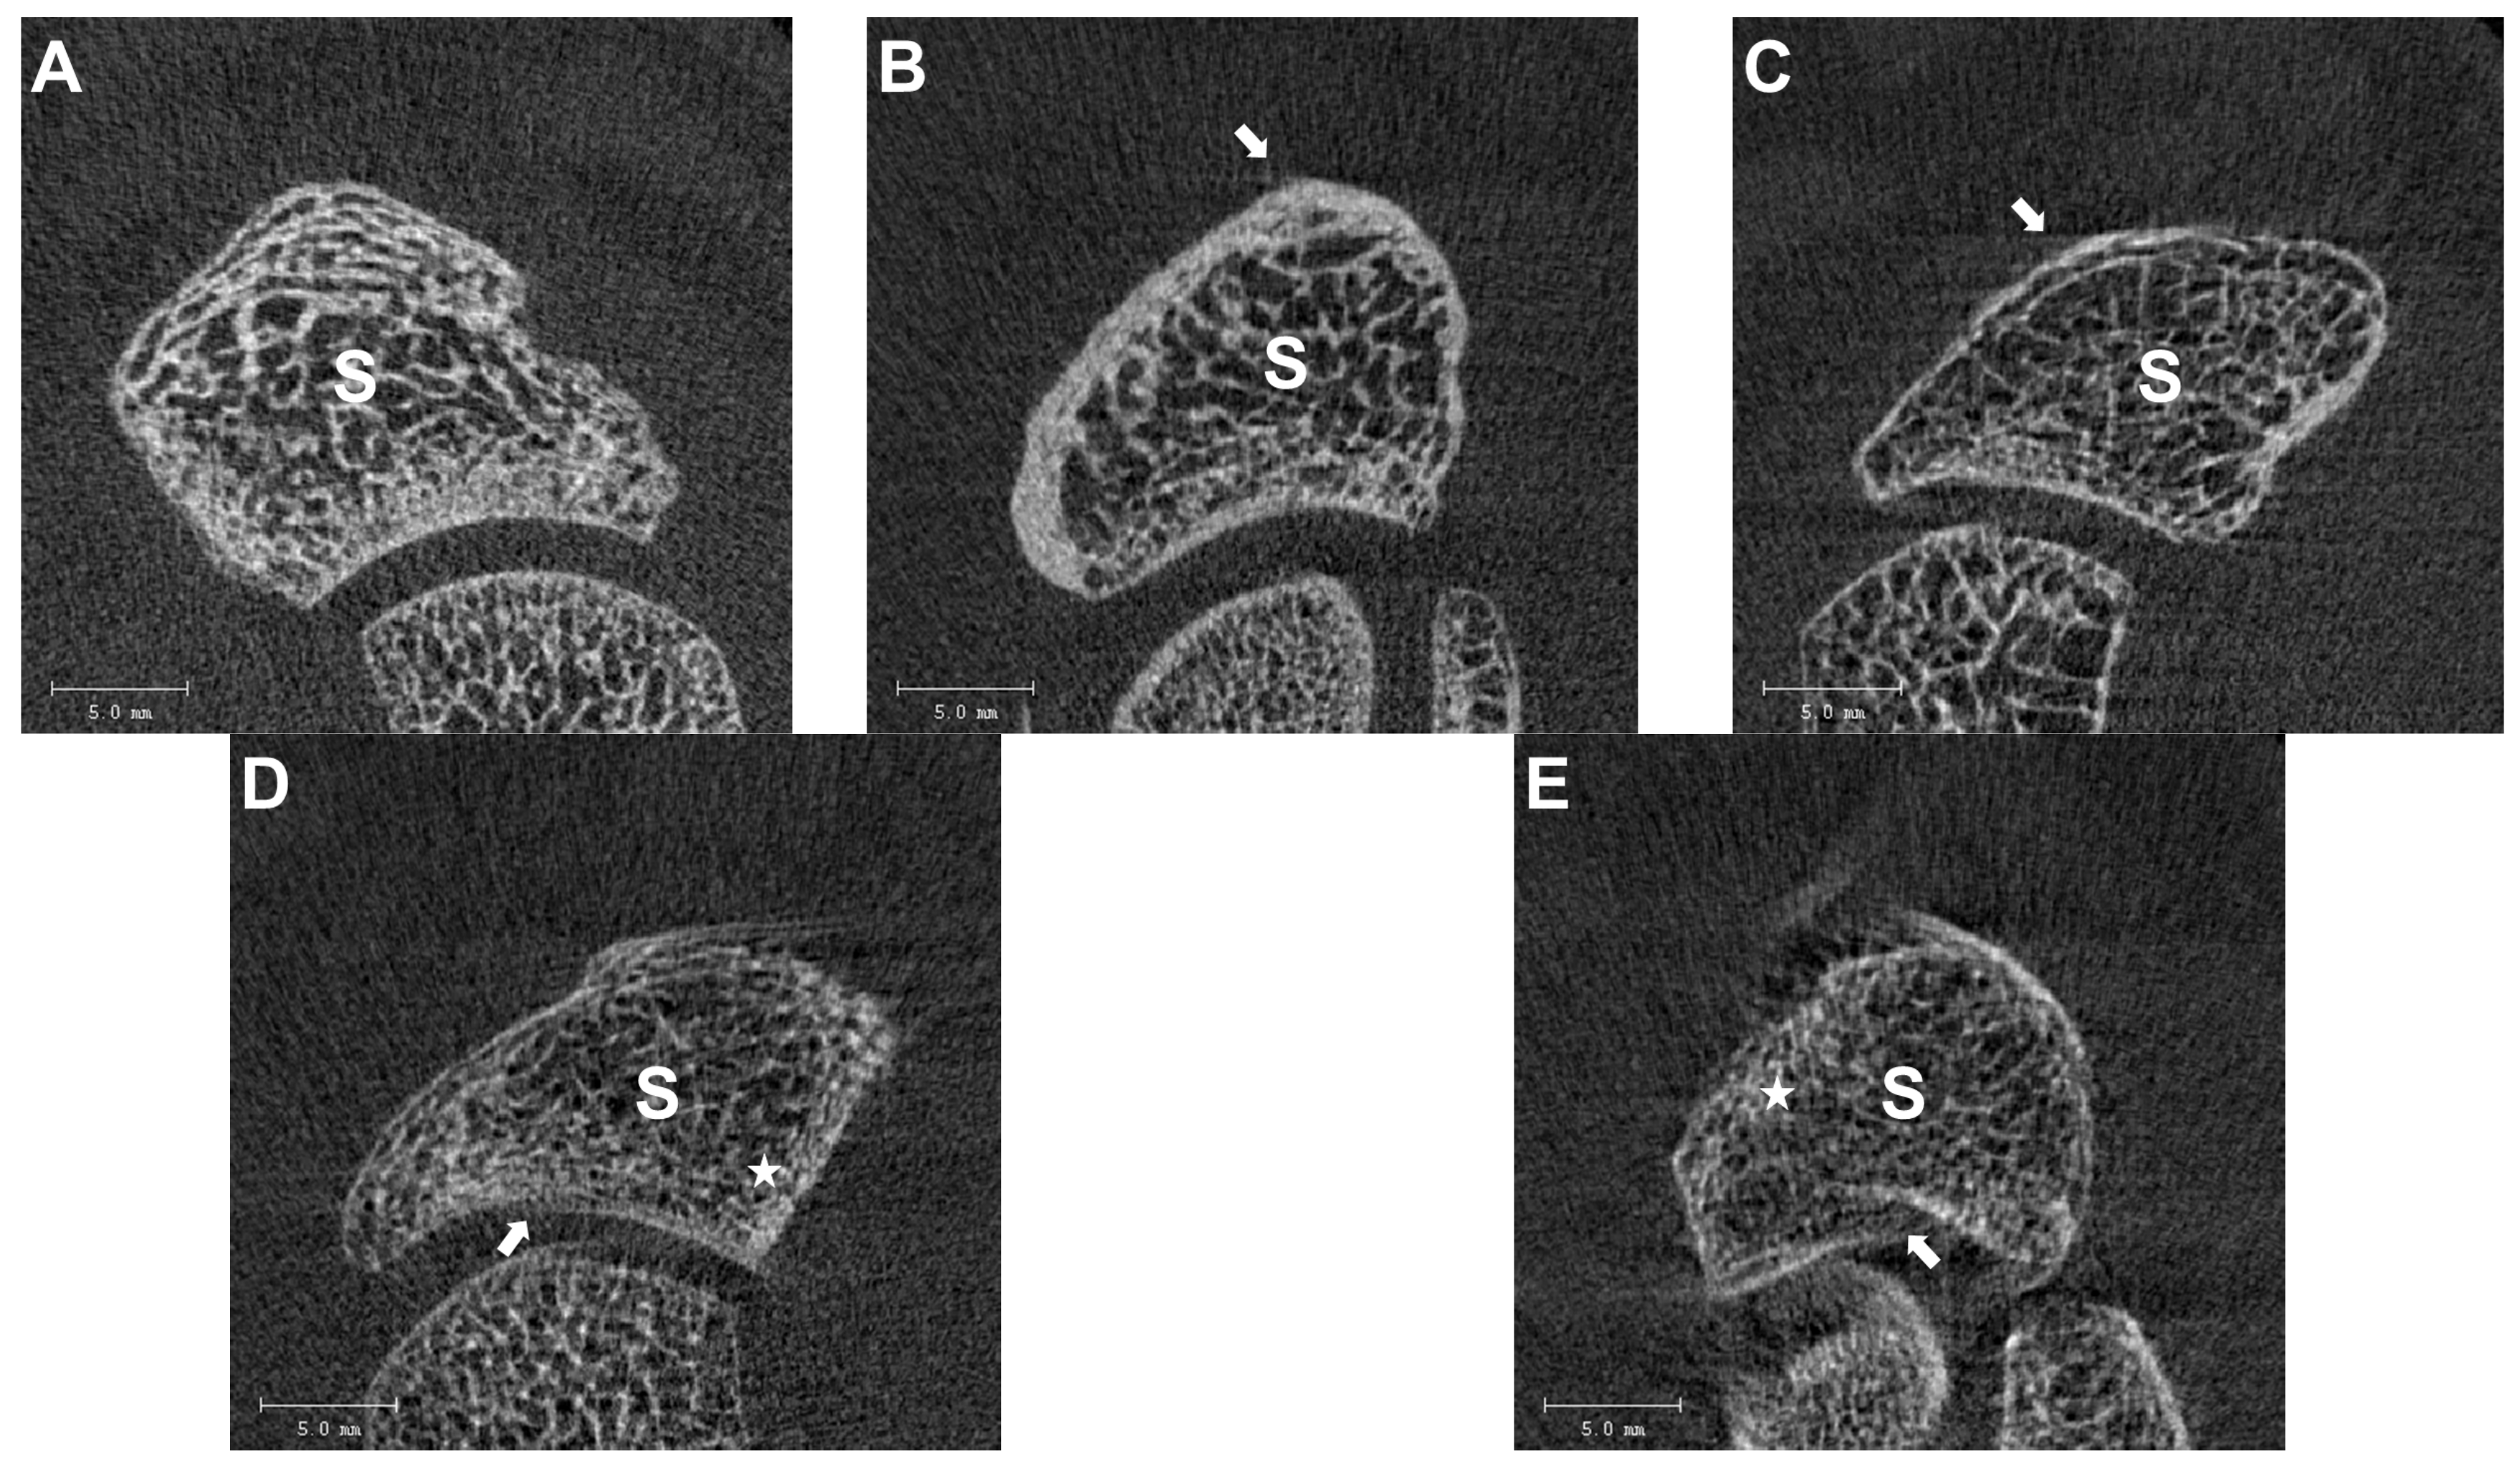

2.3. Image Quality Grading